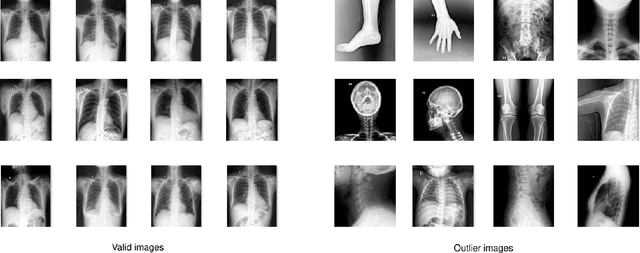

Most of the existing chest X-ray datasets include labels from a list of findings without specifying their locations on the radiographs. This limits the development of machine learning algorithms for the detection and localization of chest abnormalities. In this work, we describe a dataset of more than 100,000 chest X-ray scans that were retrospectively collected from two major hospitals in Vietnam. Out of this raw data, we release 18,000 images that were manually annotated by a total of 17 experienced radiologists with 22 local labels of rectangles surrounding abnormalities and 6 global labels of suspected diseases. The released dataset is divided into a training set of 15,000 and a test set of 3,000. Each scan in the training set was independently labeled by 3 radiologists, while each scan in the test set was labeled by the consensus of 5 radiologists. We designed and built a labeling platform for DICOM images to facilitate these annotation procedures. All images are made publicly available in DICOM format in company with the labels of the training set. The labels of the test set are hidden at the time of writing this paper as they will be used for benchmarking machine learning algorithms on an open platform.